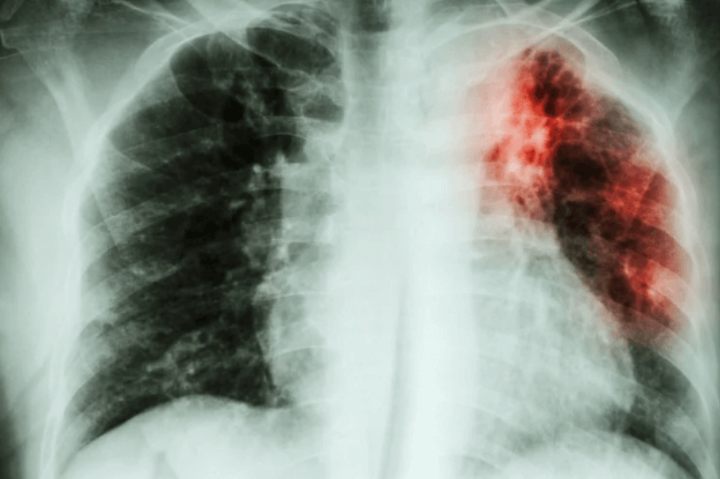

De manera, que por ejemplo en la Fibrosis Pulmonar, el efecto mencionado y sumatorio de la senescencia, produce la fibrosis de una gran parte del tejido. No es un problema de intercambio de gases cuando no es completa, sino interfiere en la movilización del pulmón en el tórax, hacia el abdomen en el efecto “acordeón” respiratorio, de expansión compresión, como se ha comprobado en modelos murinos (ratones), con daño inducido con Bleomicina (una quimioterapia con diferentes usos y muy conocida).

Los alveolos o pequeñas vejigas en el pulmón, está sometido a muchos daños crónicos ambientales, como el polvo, el humo, humo de tóxicos, los alquitranes de le los vegetales quemados, tabaquismo. Las células lanzan la alarma y nadie hace nada, las células reclutadas para la reparación inicial, va a convocar a más células senescencia secundaria, estableciendo el mecanismo de progresión, a pesar de que el daño era localizado y mínimo al inicio. Medible por el Marcador T-16 en los alveolos en muchas células senescentes alveolares, pero otras responderán al marcador P-21.